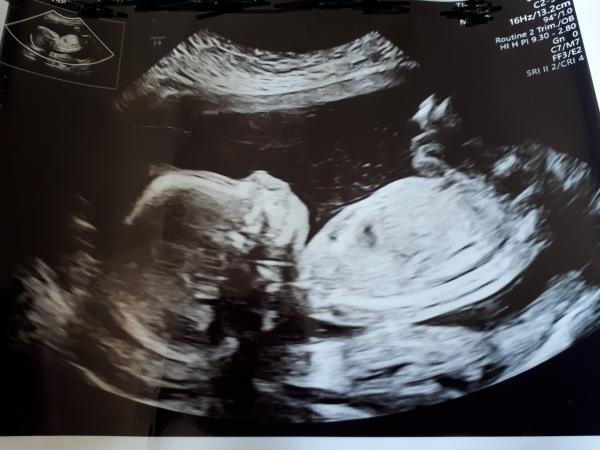

Gissa kön!

Någon som är duktig på att gissa kön på ultraljudsbild?? Nyfiken!